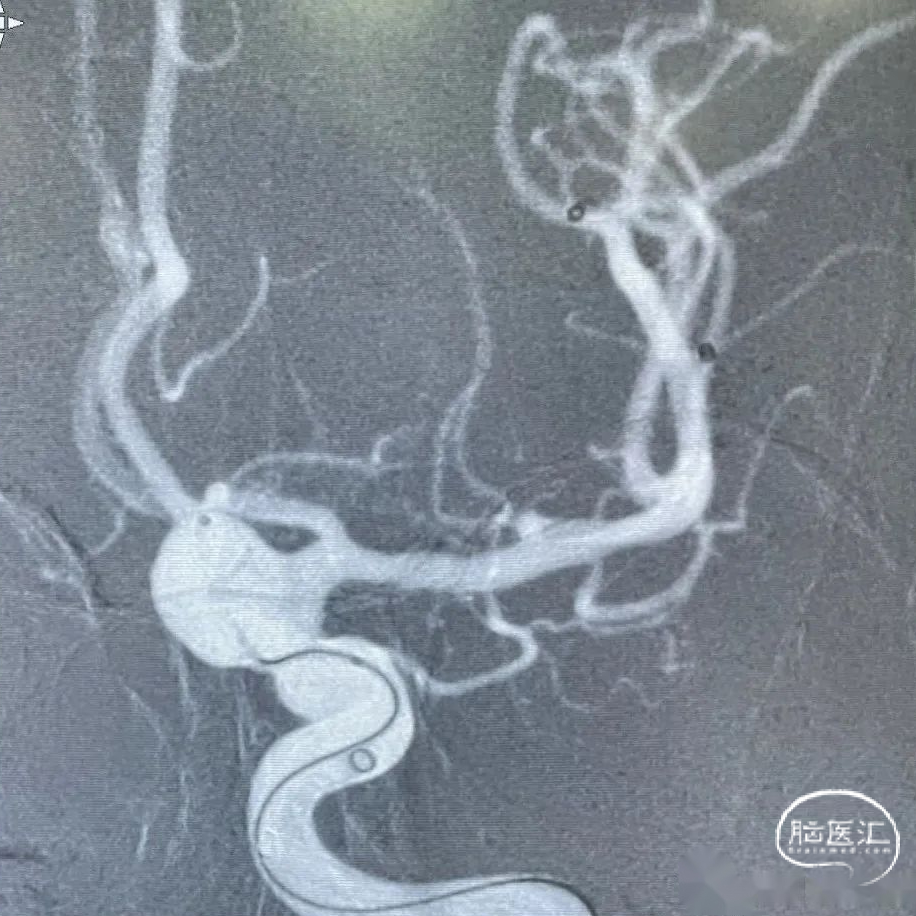

术前DSA造影:造影后发现该患者左侧后交通动脉瘤。

术前DSA造影:颈内动脉C6、7段膨大扭曲,导致C5段与M1之间形成明显的锐角。通过3D工作位测量出左侧后交通动脉瘤大小约为13.5mm*10mm*8mm:动脉瘤最大径13.5mm,载瘤动脉直径:近端5.0mm,远端3.5mm。

术后即刻影像,造影示动脉瘤腔内空虚处滞留明显,载瘤动脉通畅。遂撤出弹簧圈微导管,支架输送系统。